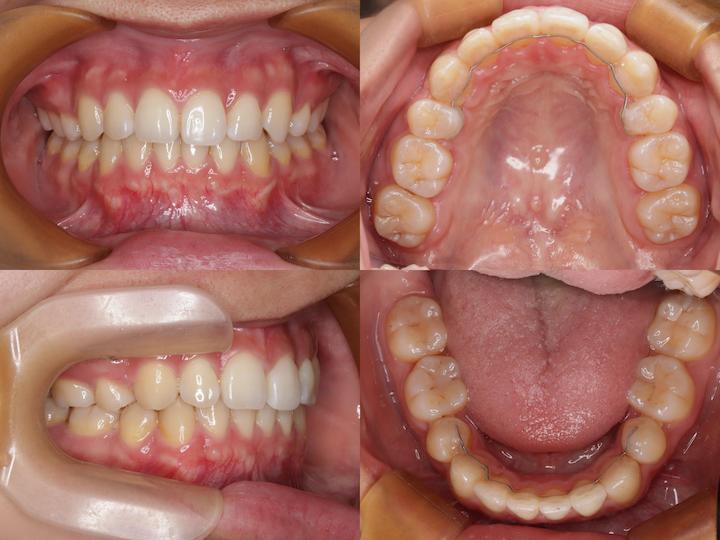

治療結果

上下顎前歯部の叢生は完全に改善され、犬歯も適切な位置に配列されました。また、AngleⅡ級臼歯関係も改善し、機能的かつ審美的に良好な咬合状態を獲得することができました。

口元の形態も治療前の良好な状態を維持しており、患者様からも高い満足度をいただいております。